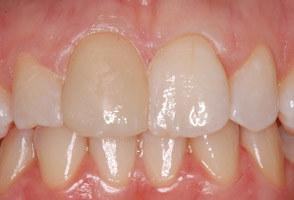

Cas 2 : 3 incisives - 2 séances de 75 minutes la même journée